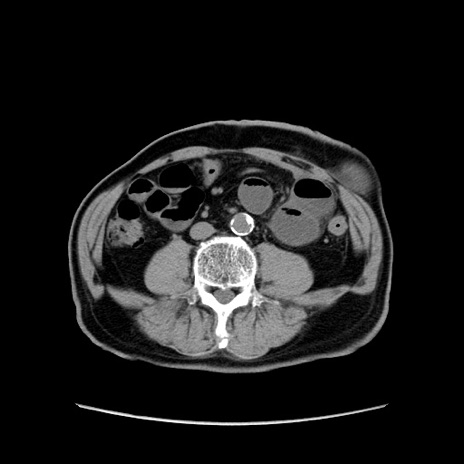

症例24(横断像)

【症例】80歳代男性

【主訴】左側腹部痛、嘔吐

【現病歴】本日早朝より左腹部に痛みあり。昼頃嘔吐認めたため、救急要請。

【既往歴】直腸癌(Mile手術)、胆摘

【身体所見】意識清明、BT 35.9℃、BP 221/93mmHg、SpO2 97%(RA) 、腹部:左ストーマ周囲に限局性の腹部膨隆あり。 膨隆部自発痛・圧痛あり・軟。

【データ】WBC 7700、CRP 0.09